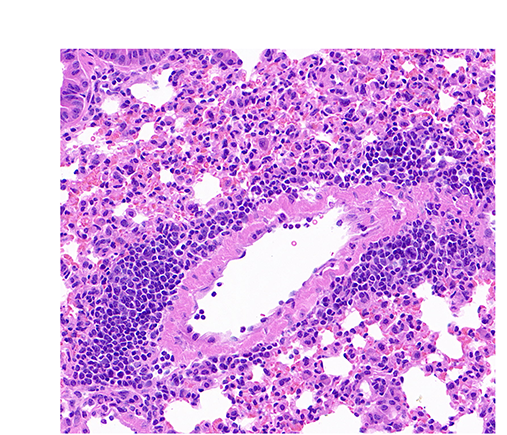

在2025-07-29日,我们展示过H&E起源版本的“银河系”(QuPath:“银河系”起源于H&E),笔者在这里尝试通过R的ggplot2(包括代码/R codes)来展示该“银河系”。

7. “银行系”的起源